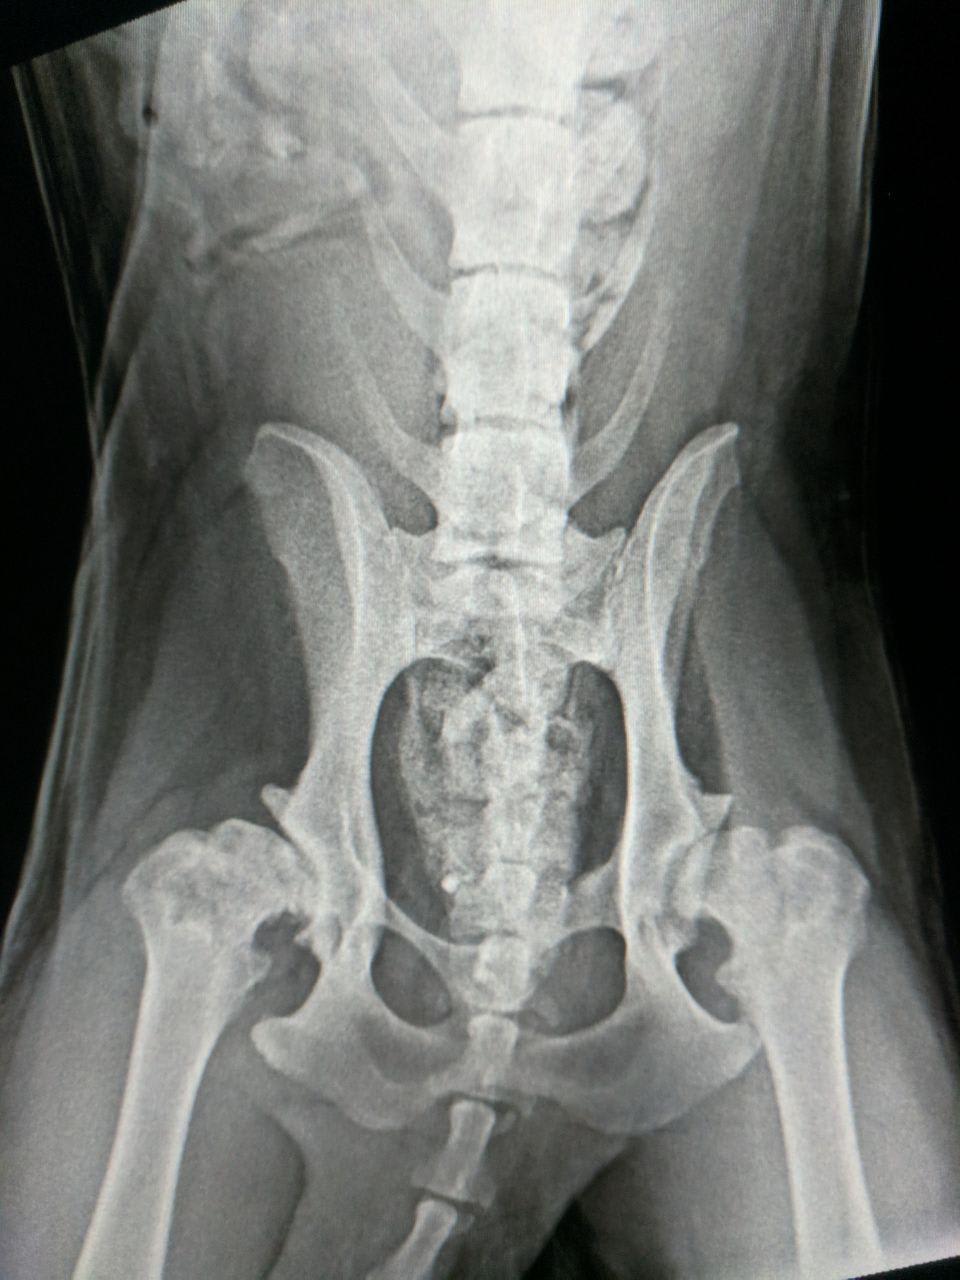

Our long hair German Sheppard is limping. She is almost 4 years old and never had any puppies. Can you have a look at MRI and advise us. Thanks

This X-ray shows she has poor hip conformation or hip dysplasia and hip arthritis. Unfortunately this is a common orthopedic problem in German Shepard dogs and othe large breeds. Most dogs respond well to weight loss if needed and dog arthritis medication prescribed by your veterinarian. By keeping her active and moving she will maintain her muscle mass which will support her hips so there is less bone rubbing, which will result in less pain. Giving joint supplements like Dasuquin or Cosequin can help in addition to Omega 3 or fish oil which will reduce some of the inflammation. Physical therapy with a rehab veterinarian is effective in maintaining her muscles and help reduce the limping. Hip dysplasia can’t be cured but it can be managed so Bella can continue to live an active life. Thanks for using Petco Pet Education Center, formerly Petcoach to help you care for Bella.